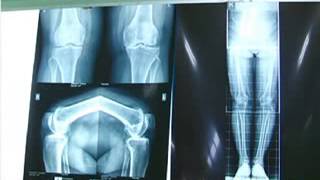

• Rs Borromeus Channel : EPS 1 OSTEOARTHITIS

Video mengenai OSTEOARTHITIS dibawakan oleh dr. Andre Yanuar , SpOT. http://www.rsborromeus.com, http://www.stikesborromeus.ac.id Rumah Sakit Santo ...